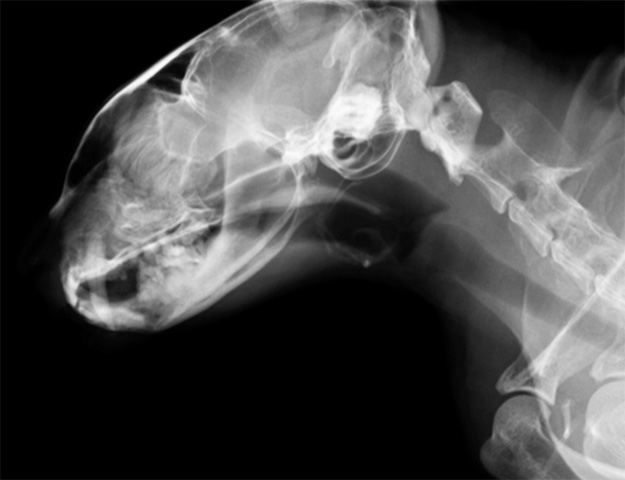

一般的なレントゲン(CR)が画像確認に1分近くかかるのに対し、当院のDR(デジタルラジオグラフィ)なら約10秒。呼吸が苦しい動物を長時間拘束することなく、迅速に診断へ移行できます。

症状に応じ、レントゲン、エコー、PCR検査、血液検査などを行います。※呼吸状態が悪い場合は、まず酸素投与を優先します。